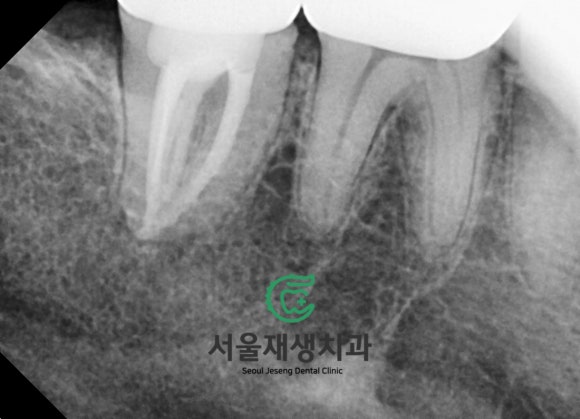

재신경치료 후 2년 6개월이 지난

지금은 과연 어떤 상태일까요?

치료 완료 당시 아주 적게 남아있던

뿌리 끝 염증이 세월의 흐름과 함께

모조리 말끔하게 사라진 모습입니다^^

뿌리 끝에 드리워져있던

약간의 검은 그림자가

말끔하게 사라진 것을 확인할 수 있습니다.